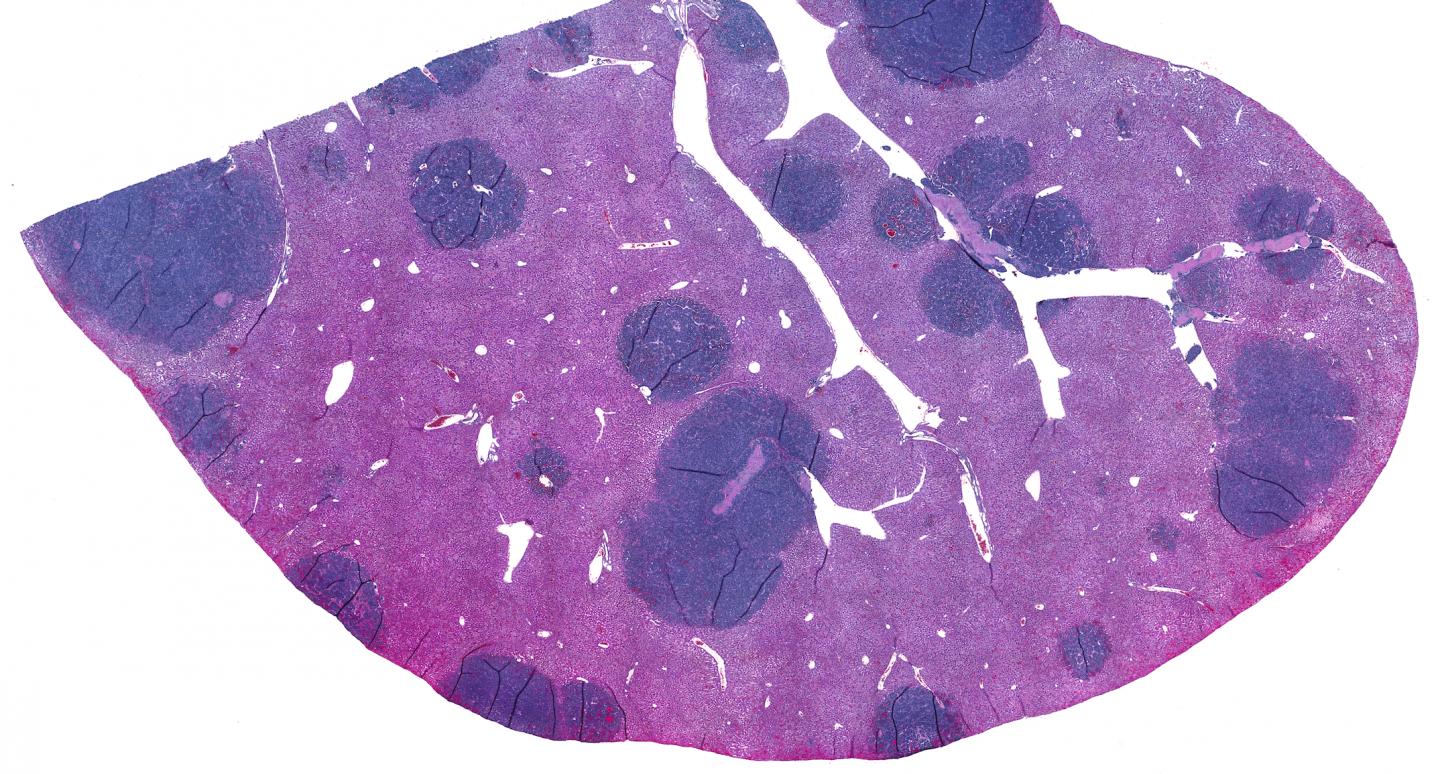

image: Small cell lung cancer (SCLC) is a highly metastatic cancer. The liver is one of the common sites of metastases, as seen in this image of mouse liver with metastatic SCLC lesions. SCLC tumors are composed of tightly packed epithelial cells with few immune cells infiltrating inside the tumor.

Data from mouse models of SCLC confirmed that the rodent version of NKG2DL was also missing from the surfaces of their cancer cells. When the researchers examined the animals' tumors, they found far fewer immune cells compared with those from mouse models of NSCLC. Additionally, the immune cells in the SCLC tumors weren't activated and therefore were unprepared to fight.